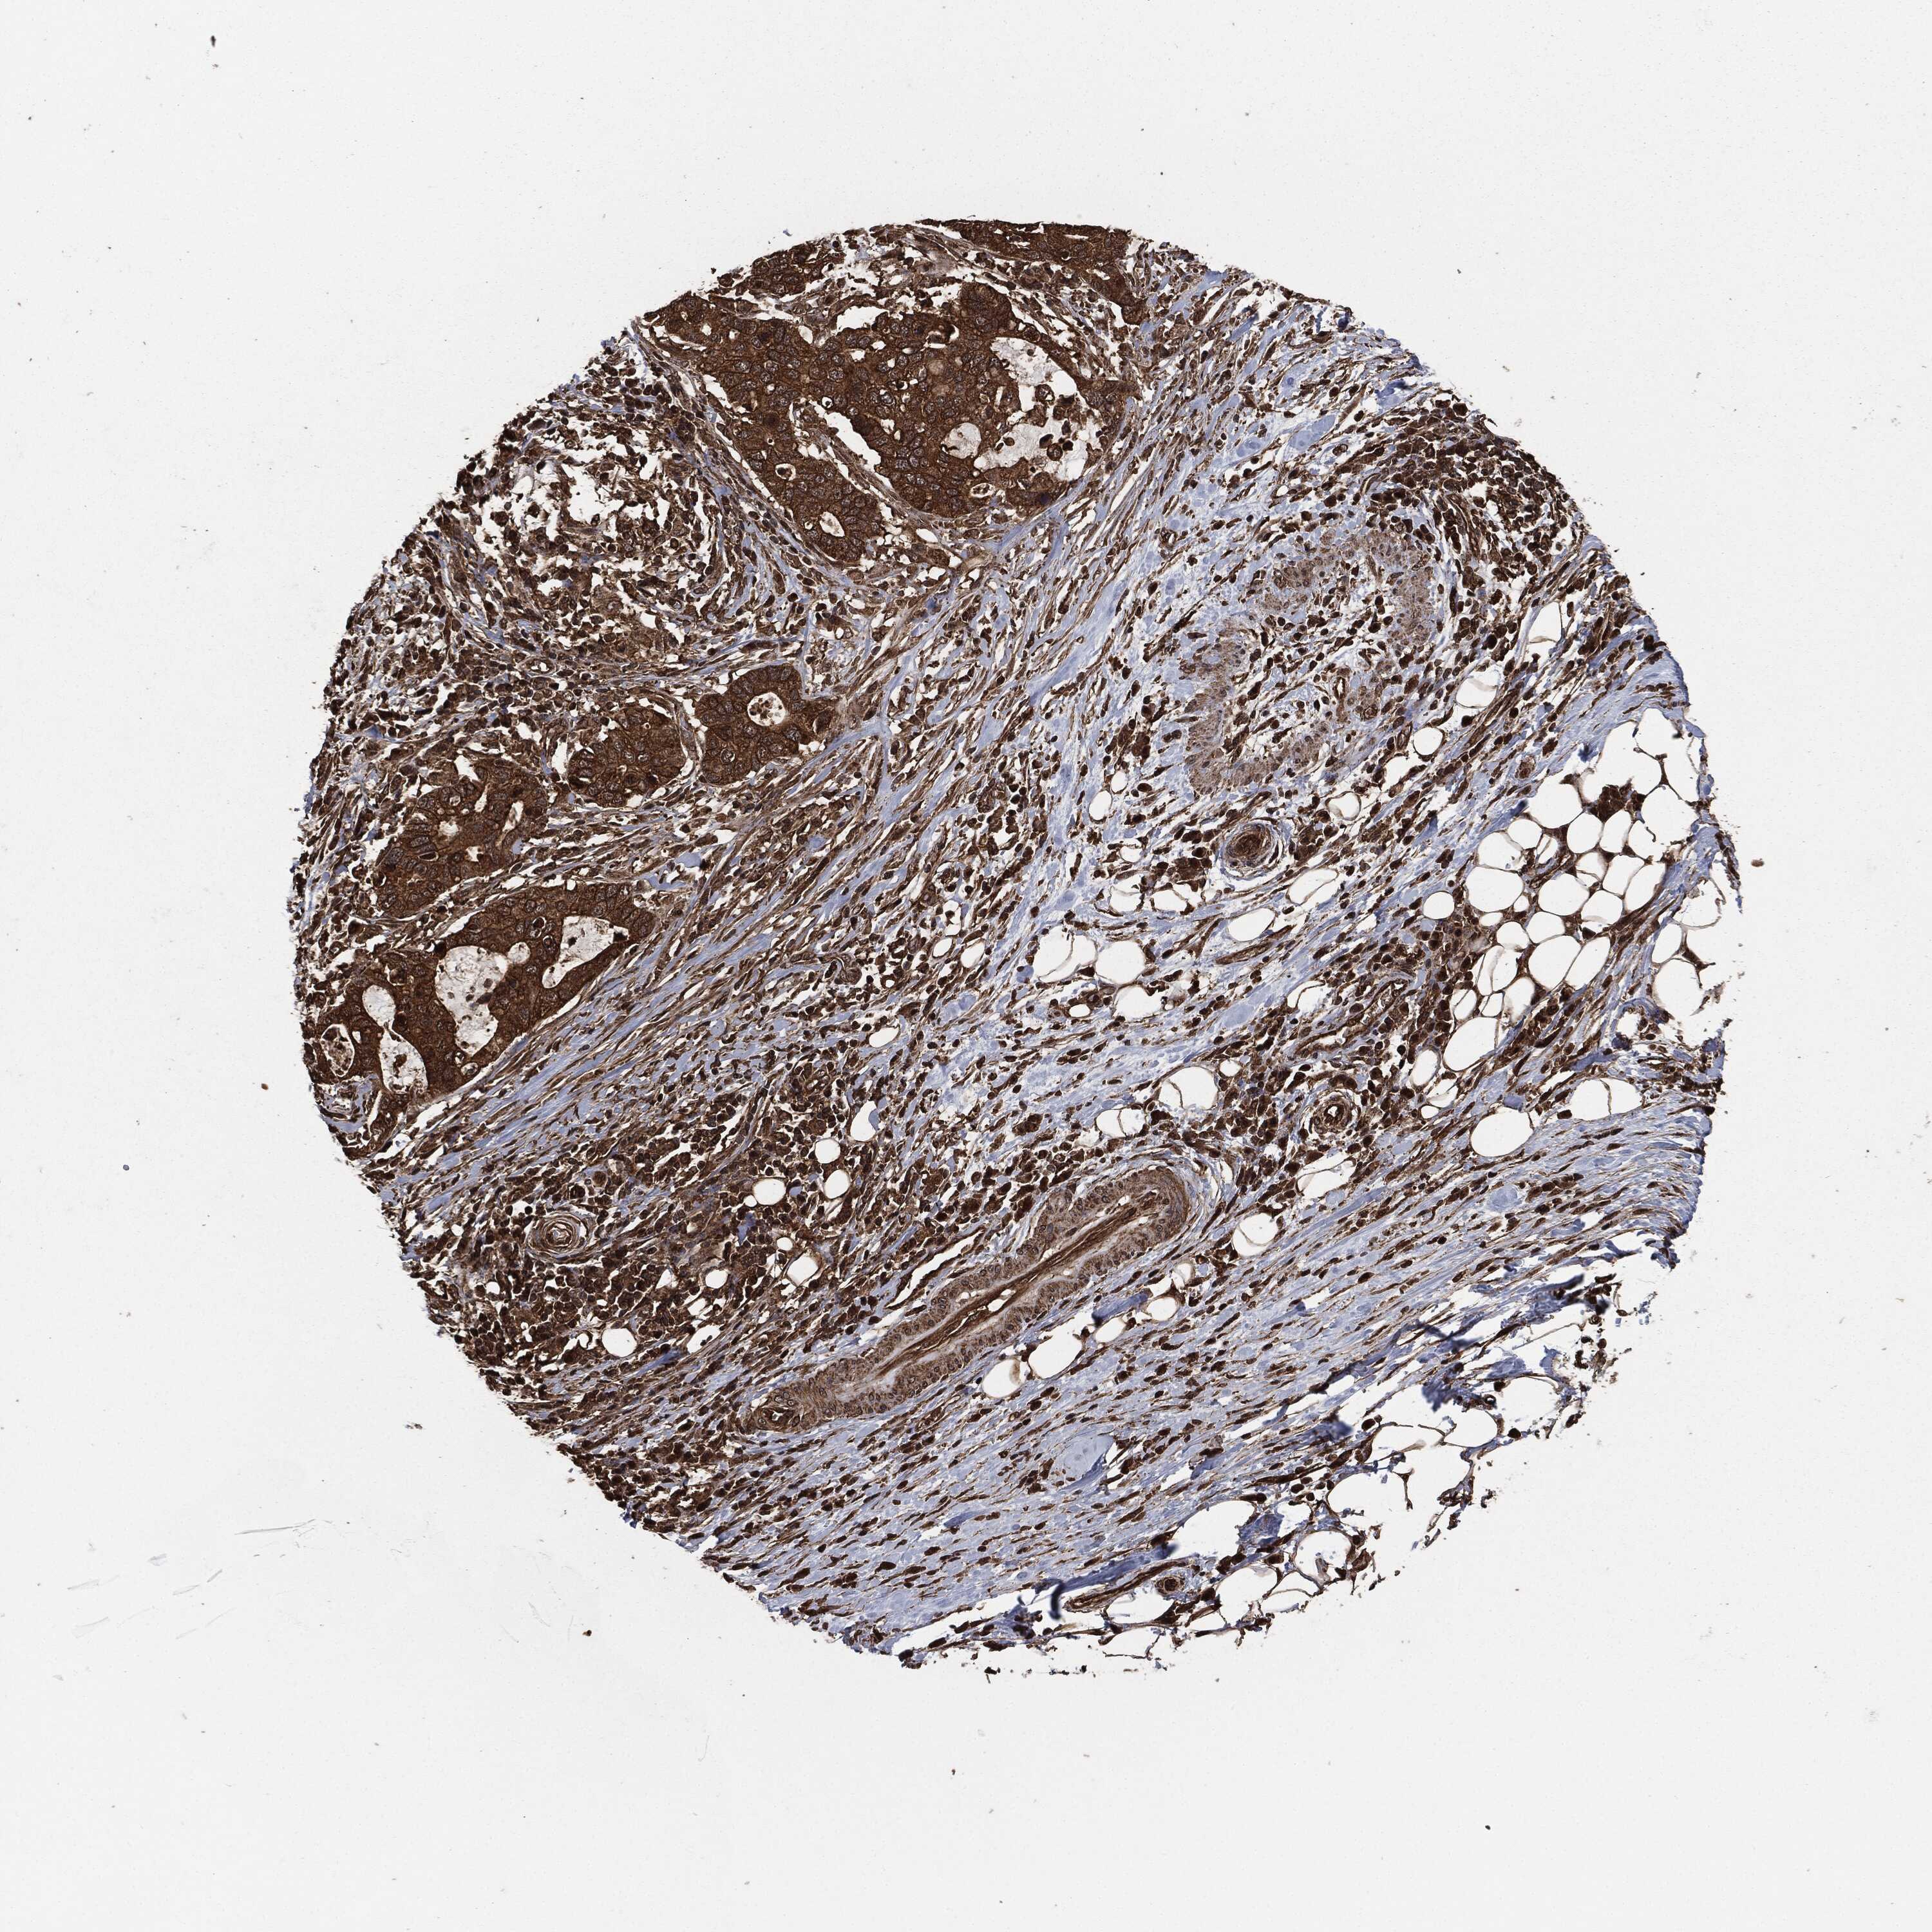

STOMACH CANCER - Protein expressioni

A mouse-over function shows sample information and annotation data. Click on an image to view it in a full screen mode. Samples can be filtered based on level of antibody staining by selecting one or several of the following categories: high, medium, low and not detected. The assay and annotation is described here.

Note that samples used for immunohistochemistry by the Human Protein Atlas do not correspond to samples in the TCGA dataset.

Antibody stainingi

Antibody staining in the annotated cell types in the current human tissue is reported as not detected, low, medium, or high, based on conventional immunohistochemistry profiling in selected tissues. This score is based on the combination of the staining intensity and fraction of stained cells.

Each image is clickable and will lead to virtual microscopy that enables deeper exploration of all samples and also displays staining intensity scores, fraction scores and subcellular localization as well as patient and tissue information for each sample.

HPA049830

CAB002015

CAB080330

CAB080331

CAB080332

Staining

High

Medium

Low

Not detected

Intensity

Strong

Moderate

Weak

Negative

Quantity

>75%

75%-25%

<25%

None

Location

Nuclear

Cytoplasmic/membranous

Cytoplasmic/membranous,nuclear

Adenocarcinoma, NOS

Adenocarcinoma, High grade